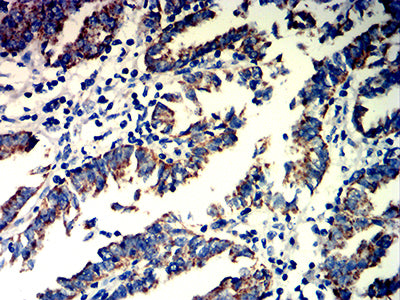

分类: 科研抗体货号: 32212别名: SMPR; MPR46; CD-MPR; MPR 46; MPR-46; CD-M6PR应用: WB,IHC,FCM反应种属: Human, Mouse